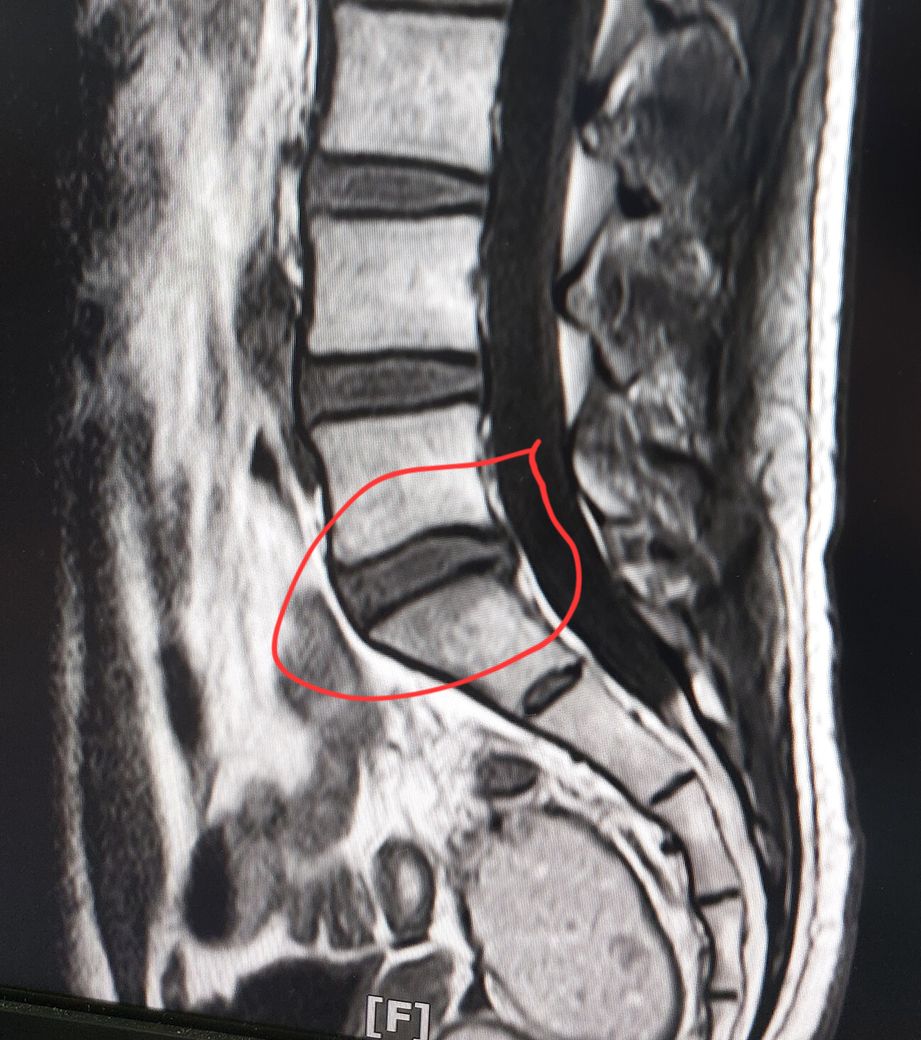

허리디스크 심한편인가요? [Mri 사진 첨부]

멸개월전부터 요추가 뻣뻣하고 시큰거리다가 최근에 좀 나아지긴 해도 만성적이라서 오늘 mri 찍고 허리디스크 진단받았습니다

(요추 맨 밑 천추 위 디스크)

• 1번 째 사진